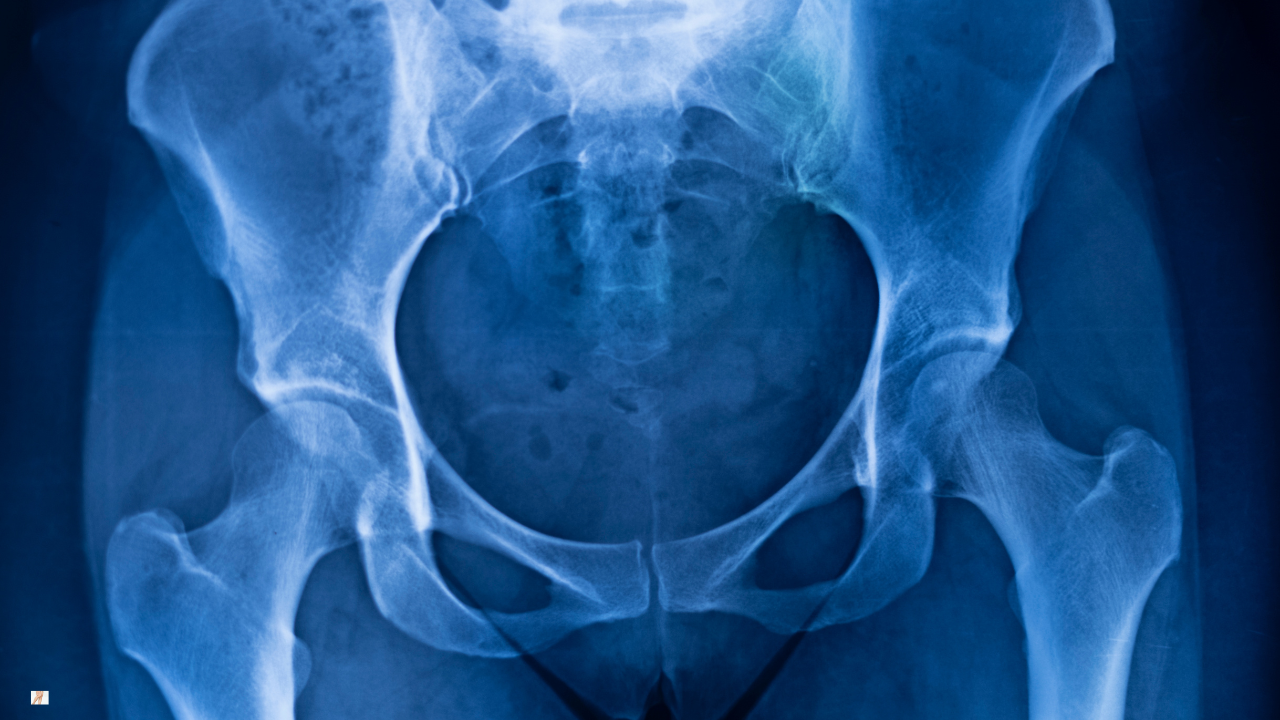

A diagnosis of acetabular dysplasia is confirmed radiographically. X-rays allow measurement of socket coverage and alignment.

An X-ray is the primary investigation used to diagnose acetabular dysplasia.

It shows the shape and orientation of the acetabulum (the socket) and how much of the femoral head is covered. Measurements such as the lateral centre-edge angle help determine whether the socket is shallow and by how much.

X-rays are particularly useful because dysplasia is a bony alignment issue. They allow clinicians to assess structural coverage and joint orientation under load.